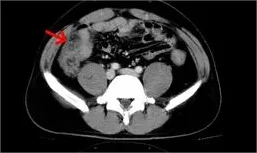

影像学检查常包括CT扫描和MRI检查,用以确定肿瘤的具体位置、大小及其对周围组织器官的侵袭情况。此外,PET-CT检查可以帮助医生评估是否存在远处转移。